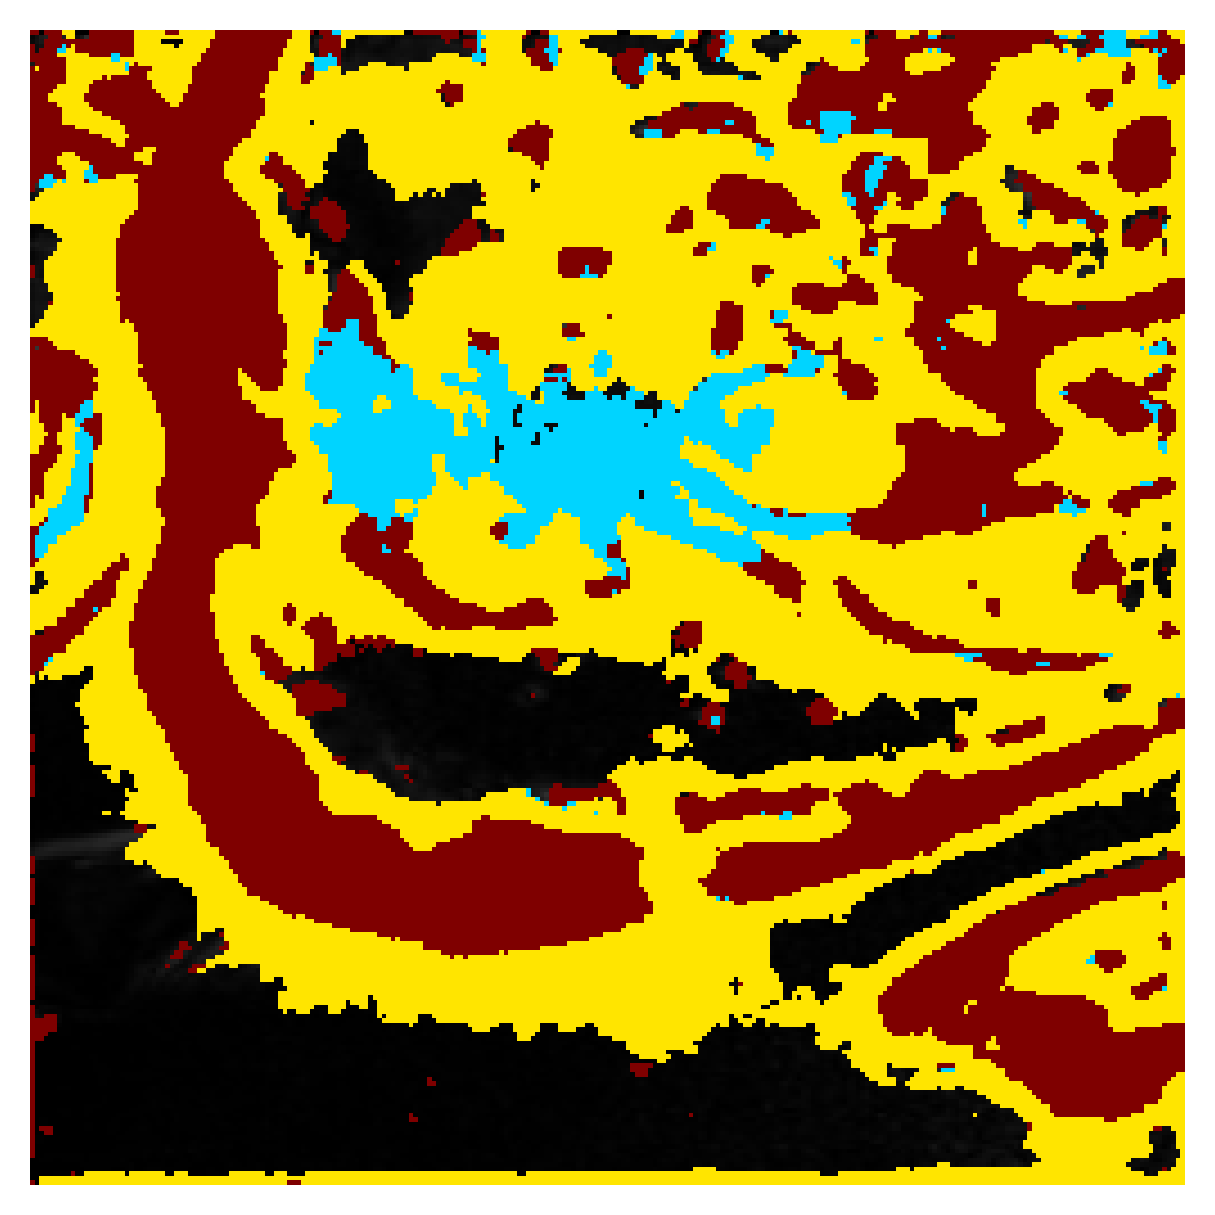

Generally, given an exact, full annotation of an object, such a Euclidean signed distance map encodes also information on the shape of an object. But when using a weak ground truth , where and , inferring a correct extent and shape of the objects is nontrivial. As shown in 1(b), Euclidean distance calculated from a point label source grows radially, regardless of the actual shape of the object, and thus makes little sense from an information point of view. Under the assumption of intra-object homogeneity and inter-object contrast (w.r.t intensities), this problem can be circumvented to a degree by using a distance function that takes also intensity values into account. An example of a commonly used distance measure with an intensity component is the Geodesic distance ([34]). Let denote a path between , with and being neighbors under a chosen adjacency relation. Reusing the notation from before, a Geodesic distance map from the boundary of the ground truth class , , can be defined as

Both the Intensity and the Minimum barrier distance are defined exclusively on the image intensity space. However, from the examples of distance map in 1(d), we can notice that the values still increase somewhat radially from the annotation. This behaviour is similar to the one of the Geodesic distance in 1(c) (which actually includes the spatial proximity in its definition), and is due to the summing operator in the general Geodesic distance definition in Equation 3. While the intensities of two neighboring pixels on a path may be the same, that will rarely be the case in real life, noise riddled images. This makes the Intensity distance function approximately monotonically increasing with increasing length of the path (in space), even on paths where the intensity is mildly fluctuating (e.g. consider a path with even pixels intensity value of and odd pixels intensity value of ). One could thus argue that such a definition of a distance, despite being based exclusively on intensities, is still capable of loosely encoding the spatial distance information.

On the other hand, while we can see that the MBD based maps are similar to Geodesic and Intensity ones (1(e)) with respect to the object shape recovery, they have a less pronounced and smooth increase in the values outward from the source point.

In contrast to Euclidean distance, the Geodesic, Intensity and Minimum barrier distance maps all encode contrast sensitivity and preserve the object structures by harnessing the intensity information of the underlying image. This holds even when calculated from point sources. In practice, using such maps for network training could mean a lower penalty for false positives that occur farther from the point annotation but are close to it in intensity. Thus still enabling the propagation of a sort of shape information (as it can be inferred from the raw image intensities).